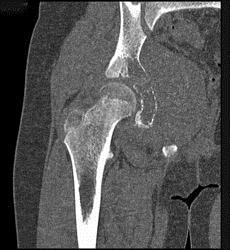

问题 男,15岁,右髋部疼痛、红肿,有压痛,皮温增高,结合图像,最可能的诊断是 ( )

选项 A、转移性神经母细胞瘤 B、骨结核 C、急性骨髓炎 D、Ewing肉瘤 E、骨肉瘤

答案 D